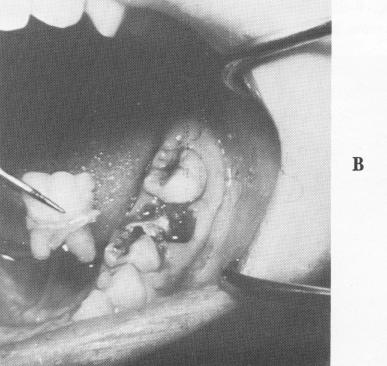

full crown restoration, the gingival tissue was retracted, and an elastic impression was taken to include the prepared tooth, the edentulous area anterior to it, and the cuspid tooth. A wax bite was also taken. A two-unit acrylic-and-gold-veneer pros-thesis was processed (Fig. 8-62). It was tried in the mouth and all necessary adjustments were made. A specially sized helical bur was then used in a contra-angle to create a hole in the desired area of bone (Fig. 8-63). An appropriate narrow ridge im-

plant was selected (Fig. 8-64), inserted into the hexagonal prolongator (Fig. 8-65), and carefully screwed into place (Fig. 8-66).

The two-unit, prefabricated splint was fitted over the implant shaft and prepared bicuspid tooth (Fig. 8-67). (If any interference occurs from such a post, a larger hole can be made on the under-surface of the abutment crown.) The bridge was then cemented into position with a hard cement (Fig. 8-68). During this procedure, as should be done during all implant interventions, x-rays were taken as guides (Fig. 8-69).